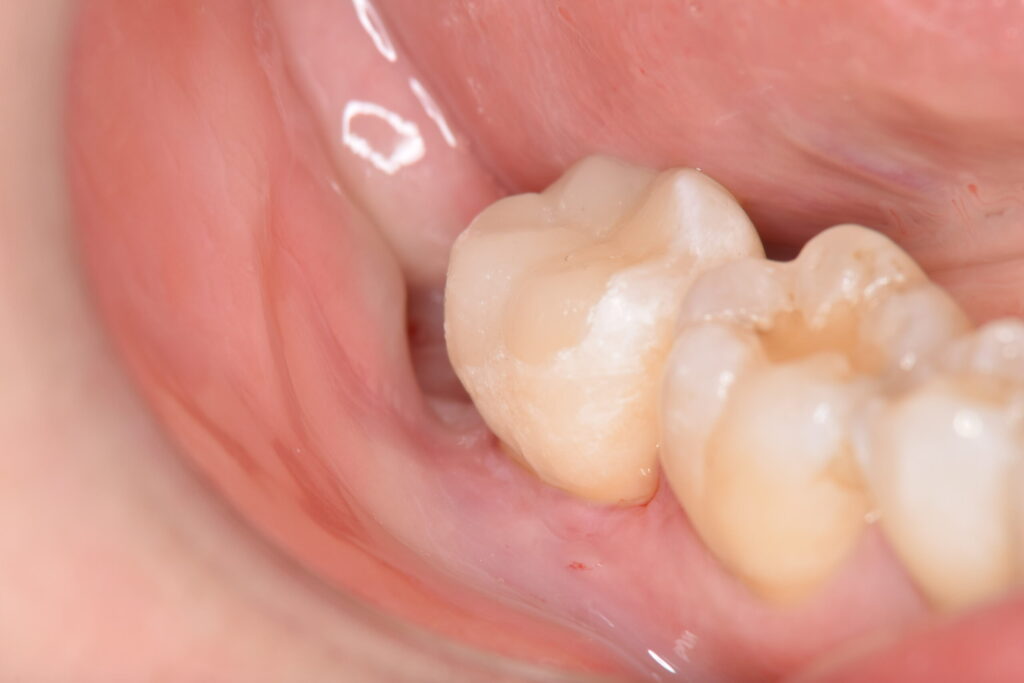

装着後のお写真です。横から見ても、全く隙間がないことが確認できます。

隙間がないことで、虫歯の再発予防に貢献してくれるでしょう。

MTAを用いたVPT(歯髄温存療法)から5ヶ月経過しておりますが、患者様は7番目の歯の痛みを訴えることなく検診に通われているため、経過は良好といえるでしょう。